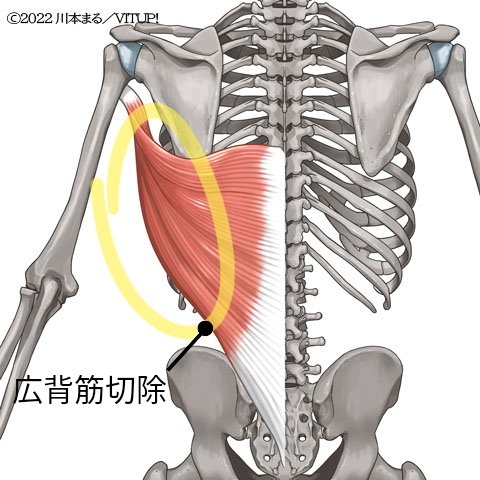

左足鼠径部を前の病院で手術したのですが瘢痕組織(傷が硬く成った組織)が大きく取れて居なかった為今回の手術を行ったのですが手術内容は左の広背筋と血管を取ってきて鼠径部に入れて血管を繋げ筋肉の働き良くし肉も血が通った肉にしてあげる って内容でした。が広背筋の切除は終わり (続く